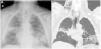

We report the case of an 82-year-old man referred to the respiratory medicine department with a 2-month history of dyspnea and desaturation, that did not improve with bronchodilator therapy. Chest X-ray showed bilateral lung consolidation, and chest computed tomography (CT) revealed areas of consolidation in right upper lobe (RUL) and left lower lobe (LUL) with associated reticulation. Given these findings, we decided to perform a fiberoptic bronchoscopy (FB) which showed diffuse endobronchial inflammation. Non-selective bronchial aspiration (BAS) and bronchoalveolar lavage (BAL) were performed during the procedure, without complications. Hours later, the patient reported an increase in his neck circumference. Chest X-ray showed subcutaneous emphysema (Fig. 1A) and an emergency CT showed pneumomediastinum (Fig. 1B). The patient was treated conservatively with analgesia and oxygen therapy, resulting in improved symptoms, so outpatient follow-up was recommended.